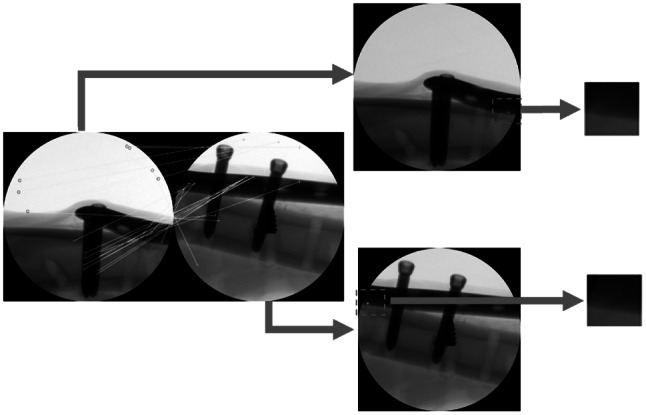

The proposed X-ray image stitching is a heterogeneous approach that includes both integrated feature detection and local image-based estimation. To extract accurate and densely matched features within the overlap region, integrated feature detection was proposed and showed superior performance compared to the conventional feature detections. To verify the effectiveness of integrated feature detection, the locations of the matched features and their pairs were compared (Fig. 5). The red circles and green crosses in each image denote locations of detected features, and the matched features are connected by yellow lines. The red translucent rectangle in the middle of each image denotes the overlap region. The integrated feature detection identified more matched features within the overlap region compared to SIFT feature detection.

Fig. 5.

Comparison of the matched features. (a) Matched features based on conventional feature detection with SIFT. (b) Matched features from the integrated feature detection